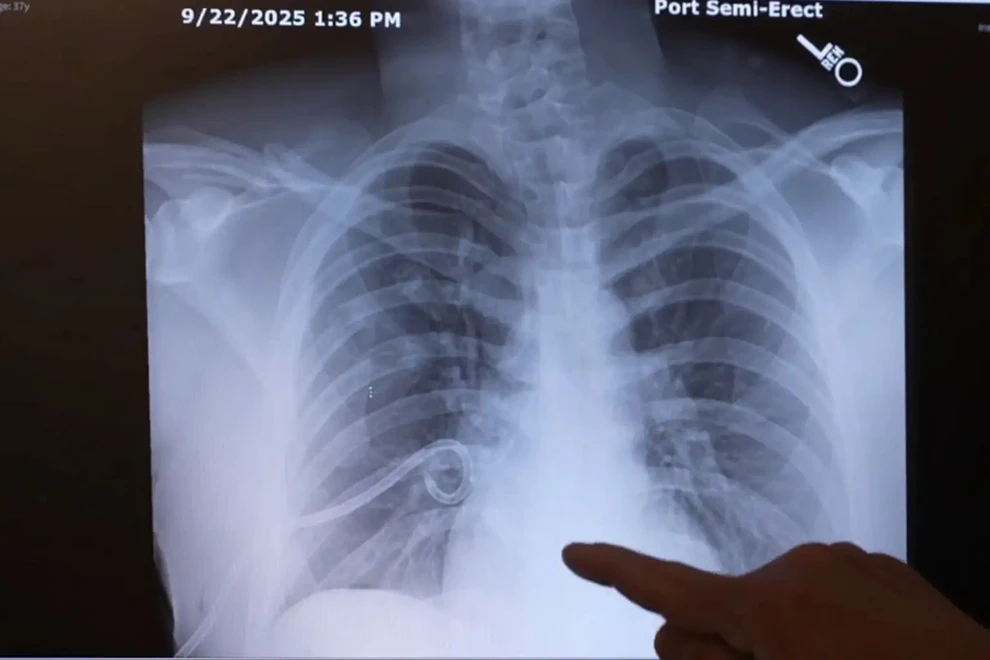

Ο Μπεμ βρέθηκε να κατρακυλά περίπου 15 μέτρα (50 πόδια) στο έδαφος, σπάζοντας την κλείδα του και επτά από τα 24 πλευρά του, ενώ υπέστη και πνευμονική κάκωση. Επίσης τραυματίστηκε σοβαρά στην πλάτη με μεγάλη τομή που προκάλεσε ο βράχος, αφού πρώτα τον είχε χτυπήσει στο κεφάλι.

Οι γιατροί στην Κλινική Billings συμφώνησαν πως θα μπορούσε να είχε πάθει «σοβαρή κρανιοεγκεφαλική κάκωση» που «θα ήταν απειλητική για τη ζωή του», αν δεν υπήρχε το κράνος, όσο φθαρμένο κι αν ήταν.